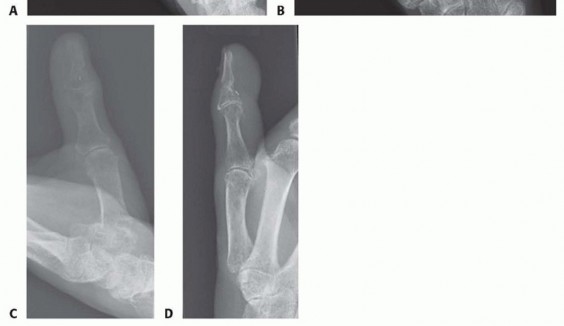

FIG 1 • A. This hand sustained sharp amputation of the digits from a table saw. The narrow zone of injury made the digits ideal for replantation. B. This hand sustained a crush injury. The resultant wide zone of injury prohibited successful replantation. Expected survival rates of replanted digits are 80% or higher, with even higher survival rates in revascularized digits.

When the patient arrives in the emergency department, standard radiographs of the amputated parts and the injured limb are obtained (FIG 4).Laboratory evaluations should include a complete blood count, basic metabolic panel, coagulation panel, drug screen, and blood type and crossmatch. Other preoperative tests are ordered as indicated by the patient's age and comorbidities.

FIG 4 • A. Standard posteroanterior (PA) radiograph of the injured hand. B. A radiograph of the amputated parts is also obtained by placing the bag containing the parts directly on the x-ray cassette.